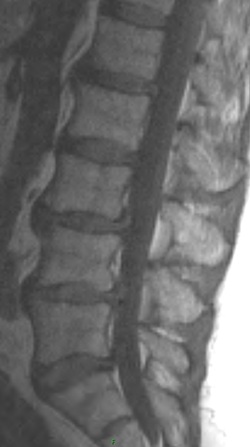

There is evidence of a grade 1 anterolisthesis of L3 on L4. The second set of images show non acute bilateral pars fractures at L3, responsible for the anterolisthesis.

The patient has an isthmic spondylolisthesis of L3. This is a unique case in that L5 is by far the most common location for this type of spondylolisthesis, with L4 less common, and L3 even more uncommon.